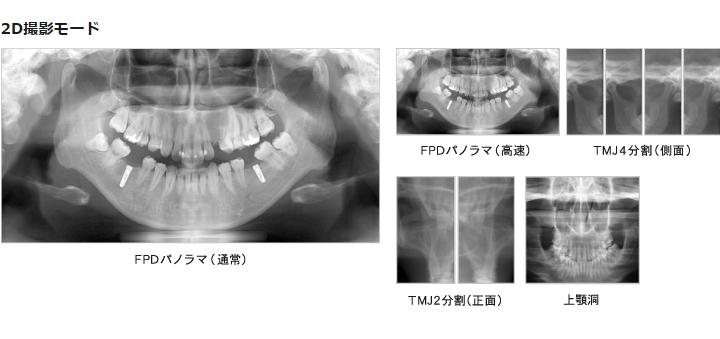

当院のCTは3Dの立体映像に加え従来のデジタルレントゲンと同様に2D(平面)画像も撮影することができます。